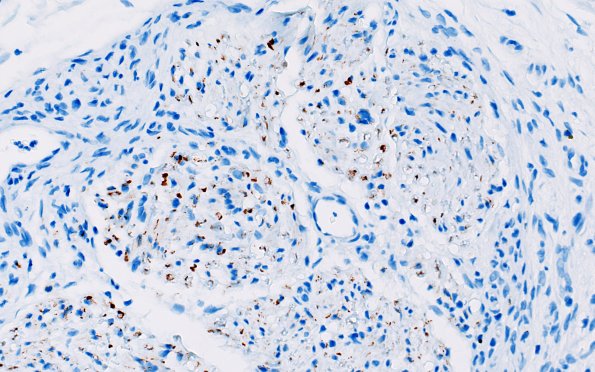

There has been significant loss of axons, particularly absent are large axons. The perineurial cells do not enclose mini-fascicles with axons. (NF IHC)